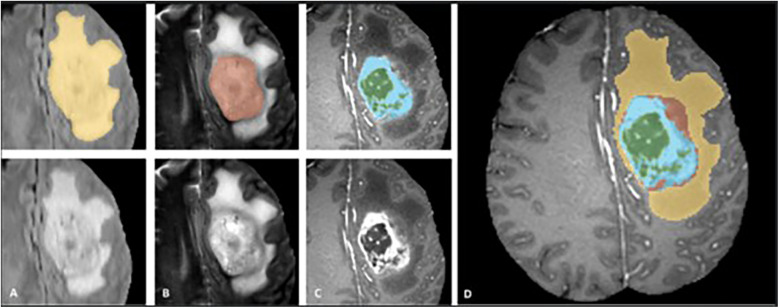

Methods: We trained a 3D U-Net DL model using the annotated 2018 MICCAI BraTS dataset (training dataset, n = 285), focusing on sub-segmenting enhancing tumor (ET) and tumor core (TC). We compared the performances of models trained on four different combinations of MRI sequences: T1C-only, FLAIR-only, T1C + FLAIR and T1 + T2 + T1C + FLAIR to evaluate whether a smaller MRI data subset could achieve comparable performance. We evaluated the performance on the four different sequence combinations using 5-fold cross-validation on the training dataset, then on our test dataset (n = 358) consisting of samples from a separately held-out 2018 BraTS validation set (n = 66) and 2021 BraTS datasets (n = 292). Dice scores on both cross-validation and test datasets were assessed to measure model performance.